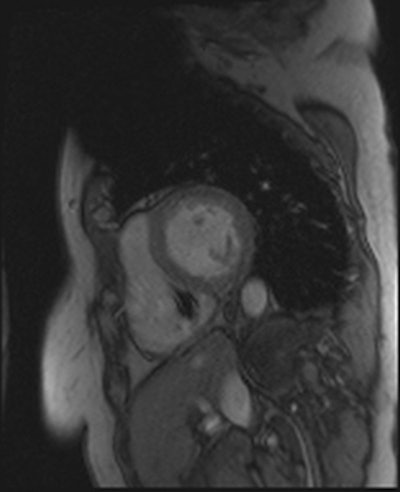

Artifacts are shown in cardiovascular MR patient imaged using spoiled gradient echo cine sequences in short-axis and two-chamber planes. Images courtesy of Touko Kaasalainen.